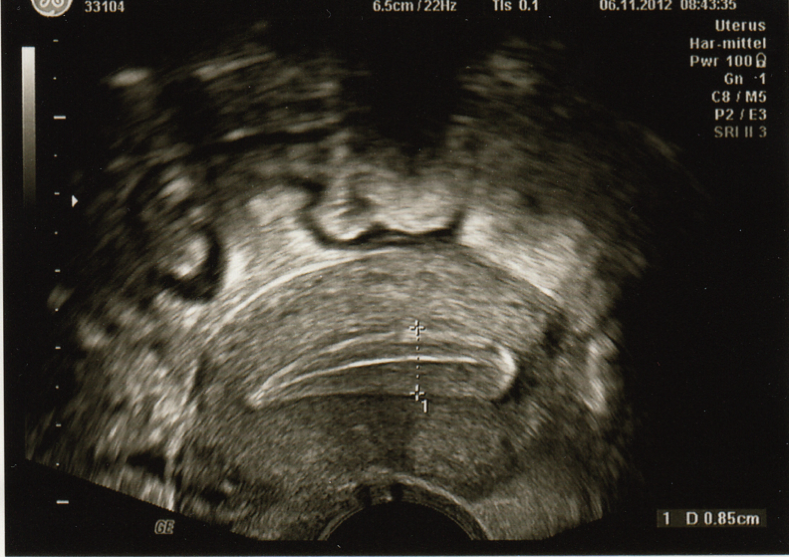

← Ultraschall-Diagnostik

Endometrium

By g78resPu | Published 06/11/2012 | Full size is 789 × 557 pixels